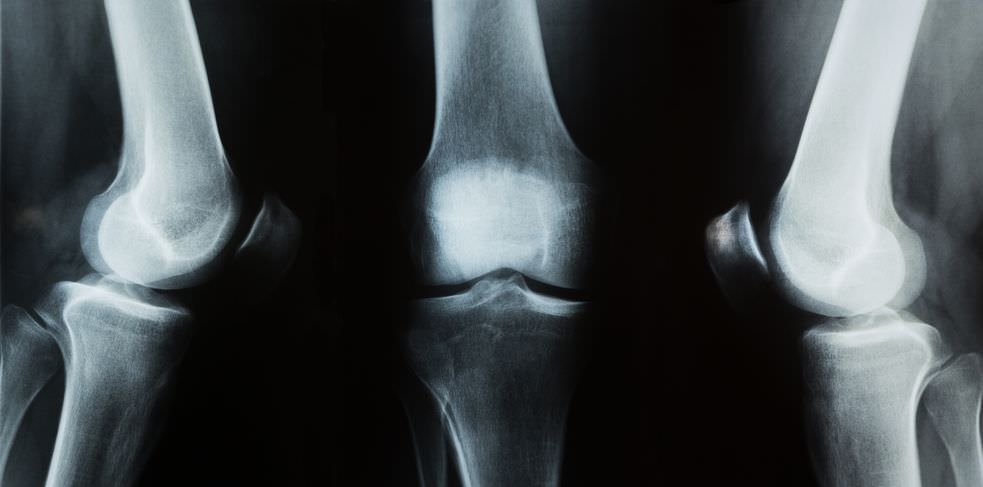

Διάγνωση ρήξης μηνίσκου

Φυσική εξέταση

Η κλινική εξέταση ενισχύει τη διάγνωση:

Πρόκληση πόνου με την πίεση στην έσω ή έξω σχισμή της άρθρωσης, με την υπερέκταση (ρήξη πρόσθιου κέρατος έσω μηνίσκου), με τη στροφική κίνηση της κνήμης επί του μηρού (στην έξω στροφή σε ρήξη έσω μηνίσκου, στην έσω στροφή σε ρήξη του έξω μηνίσκου).

Επίσης, είναι δυνατόν να υπάρχει ύδραθρο, μόνιμο ή υποτροπιάζον, ενώ η ανεύρεση θετικού σημείου McMurray βοηθάει απόμα περισσότερο, με το γόνατο σε κάμψη, η κνήμη φέρεται σε εξωτερική στροφή και απαγωγή αν πρόκειται να ελεγχθεί ο έσω και σε εσωτερική στροφή και προσαγωγή αν πρόκειται να ελεγχθεί ο έξω μηνίσκος και σιγά σιγά εκτείνεται. Συγχρόνως, πιέζεται η έσω ή η έξω σχισμή της αρθρώσεως. Το σημαίο McMurray θεωρείται θετικό, όταν με τις κινήσεις αυτές προκαλείται οξύς πόνος και αίσθημα αναπηδήσεως.

Όταν το ιστορικό και η κλινική εικόνα δεν μπορούν να θέσουν την διάγνωση, χρειάζεται να γίνει αρθρογράφημα ή αρθροσκόπηση γόνατος.

Στο αρθρογράφημα εισάγεται στο γόνατο σκιερή ουσία που γεμίζει τα κενά της αρθρώσεως και υποβοηθάει στην αναγνώριση των ρήξεων των μηνίσκων.

Στην αρθροσκόπηση επισκοπείται το γόνατο με ειδικό όργανο, το αρθροσκόπιο και αναζητούνται τυχόν εσωτερικές βλάβες των μηνίσκων, των χιαστών συνδέσμων, των χόνδρων ή του αρθρικού υμένα.

Παρόλα αυτά αρκετές φορές η διάγνωση δεν είναι σαφής. Χρειάζεται προσοχή στην απόφαση για εγχείρηση.

Σε αμφίβολες περιπτώσεις ή σε ελαφρά και ανεκτά ενοχλήματα είναι προτιμότερη η αναμονή. Χορηγούνται αντιφλεγμονώδη φάρμακα, αποφεύγονται οι αθλοπαιδιές και οι βίαιες κινήσεις και περιμένετε.

Αφού παρατηρήσει τα συμπτώματα, ένας γιατρός μπορεί να εκτελέσει κλινικές δοκιμές για να προσδιορίσει εάν ο πόνος προκαλείται από συμπίεση και πρόσκρουση ενός σχισμένου μηνίσκου. Το γόνατο εξετάζεται για διόγκωση. Στα δάκρυα του μηνίσκου, η πίεση στην γραμμή της άρθρωσης στην πληγείσα πλευρά, συνήθως, προκαλεί ενόχληση.

Η δοκιμή Steinmann (με τον ασθενή που κάθεται) και η δοκιμή  Apley (ένας ελιγμός με το γόνατο να λυγίζει 90 °). Η κάμψη του γόνατος είναι συνήθως ένας επώδυνος ελιγμός αν ο μηνίσκος είναι σκισμένος. Το εύρος της κίνησης της άρθρωσης περιορίζεται συχνά.

Το σημείο του Cooper είναι παρόν σε πάνω από το 92% των δακρύων μηνίσκου. Είναι ένα υποκειμενικό σύμπτωμα του πόνου στο προσβεβλημένο γόνατο όταν γυρίζει ο ασθενής στο κρεβάτι τη νύχτα. Ο οστεοαρθριτικός πόνος εμφανίζεται με βαρύτητα, αλλά το δάκρυ του μηνίσκου προκαλεί πόνο με κίνηση συστροφής του γόνατος από το θραύσμα του μηνίσκου, και η προσαρμογή της κάψας γίνεται με τέντωμα, προκαλώντας πόνο.

Εάν η διάγνωση δεν είναι ξεκάθαρη από το ιστορικό και την εξέταση, οι μηνίσκοι μπορούν να απεικονιστούν με απεικόνιση μαγνητικού συντονισμού. Αυτή η τεχνική αντικατέστησε την αρθρογραφία.

Σε απλές περιπτώσεις, η αρθροσκόπηση του γόνατος επιτρέπει γρήγορη διάγνωση και ταυτόχρονη θεραπεία. Τα πρόσφατα κλινικά δεδομένα δείχνουν ότι η μαγνητική τομογραφία και οι κλινικές δοκιμές είναι συγκρίσιμες στην ευαισθησία και την εξειδίκευση όταν γίνεται έλεγχος για ένα δάκρυ μηνίσκου.